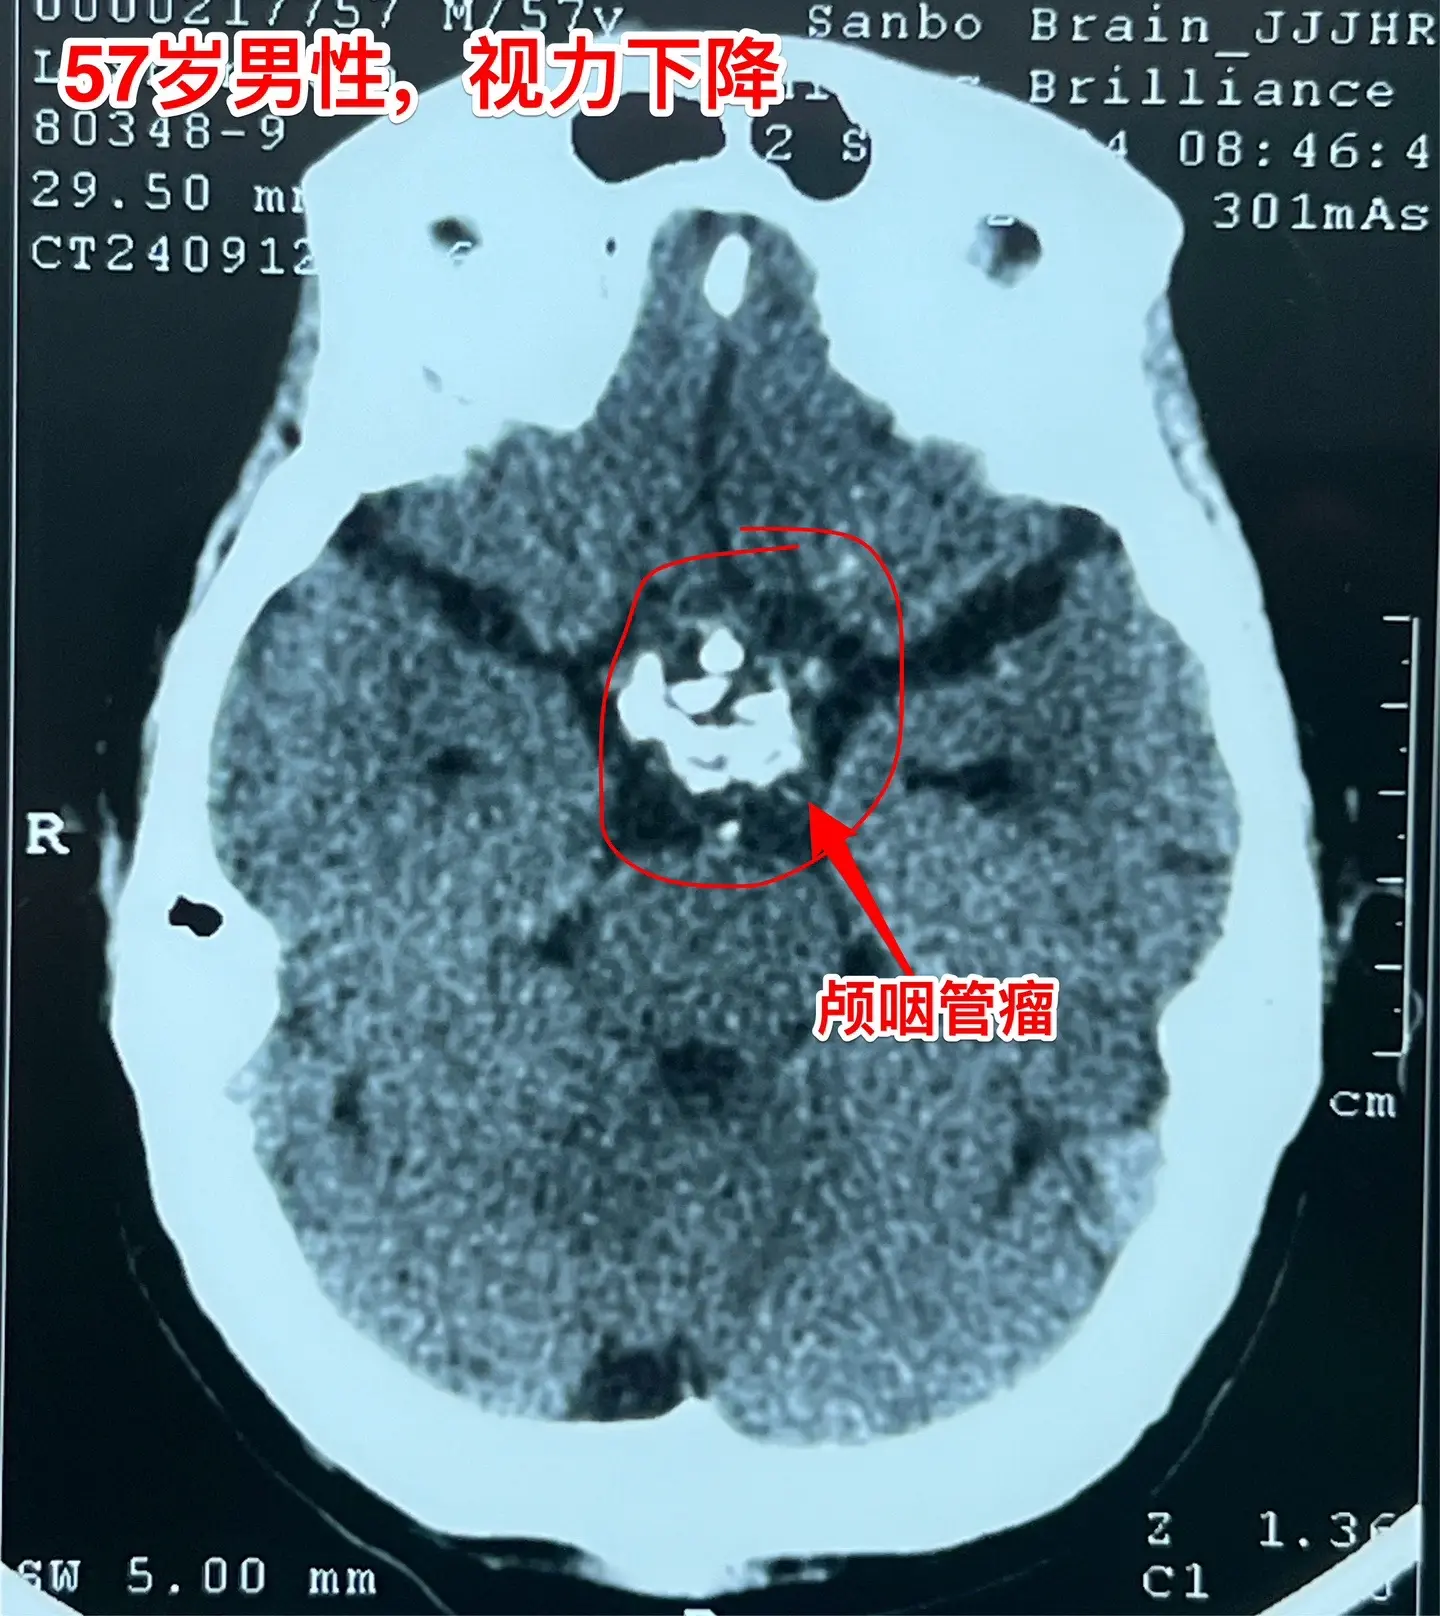

57岁男性,颅咽管瘤导致视力下降。病人因视力下降、消瘦到外院检查发现颅咽管瘤。如图所示,肿瘤体积比较大,有大量的钙化斑,是典型的造釉性颅咽管瘤。2024.9.20在我院行开颅手术,将颅咽管瘤完全切除。手术后患者视力明显改善了。十一前已经出院了,出院前体重有增长。